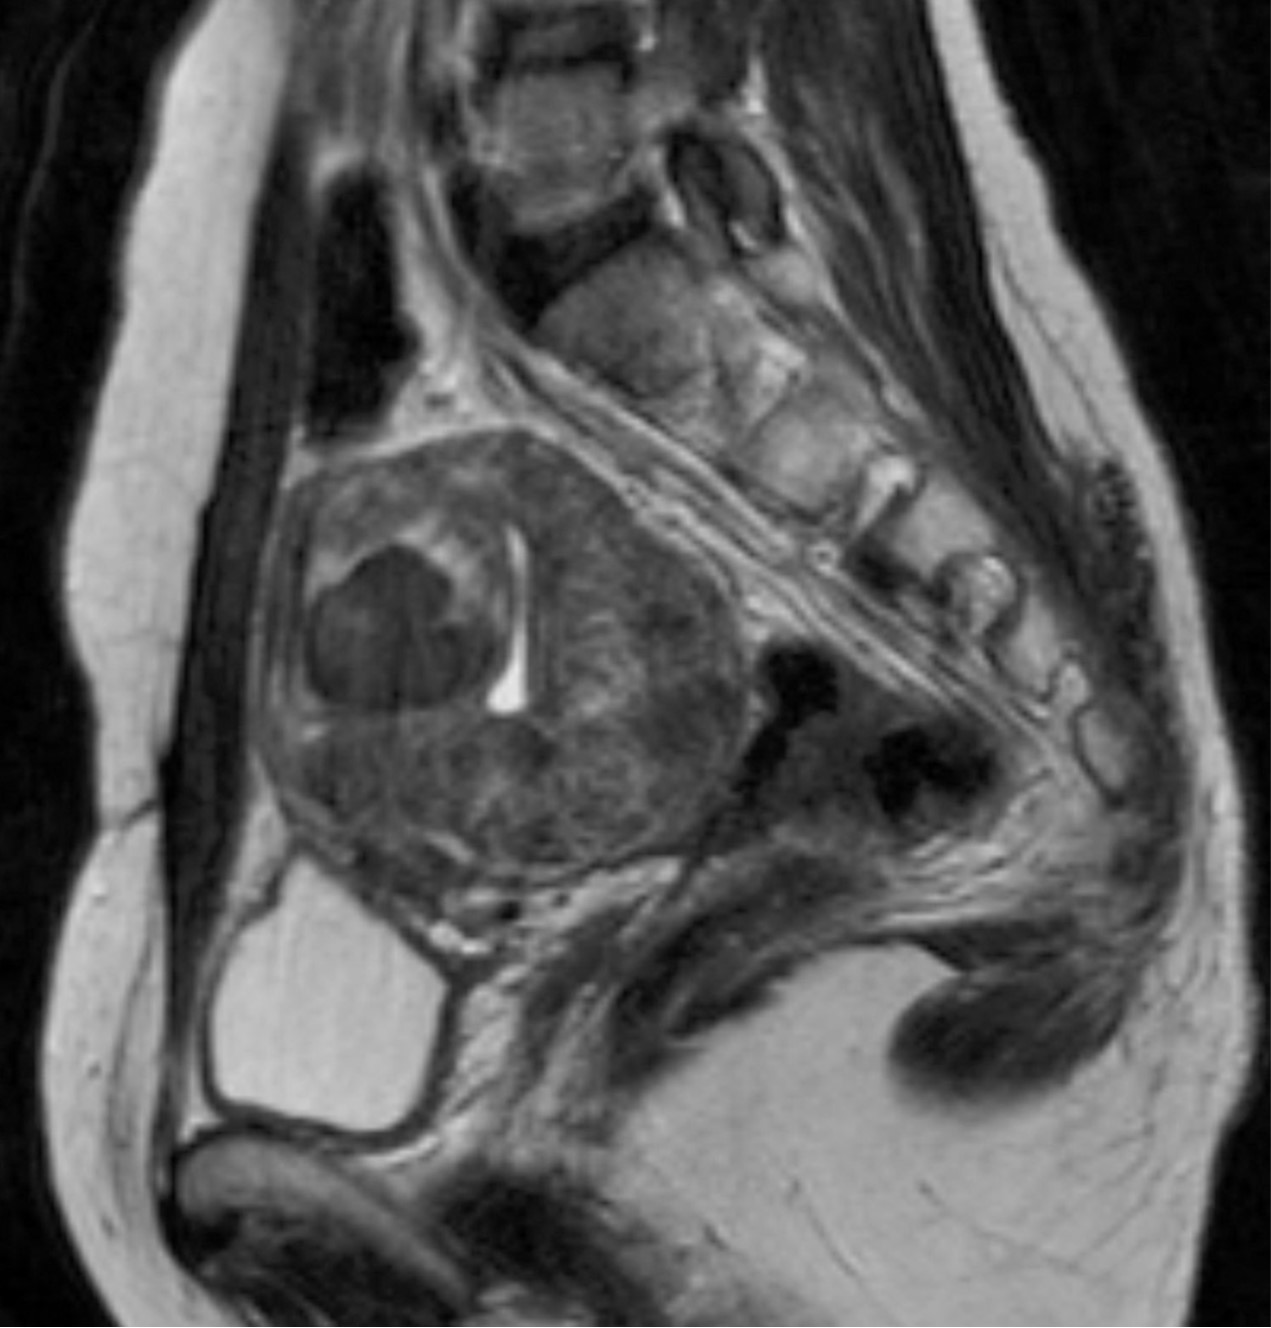

Fig. 3.

Fig. 3. T2-weighted sagittal MR image obtained 3 months after uterine artery embolization shows necrotic changes in most uterine myomas. The largest one shows 84.4% volume reduction.

초음파 유도 하에 우측 대퇴동맥을 천자하여 5F sheath(Terumo, Tokyo, Japan)를 삽입하였다. Pigtail 카테타(Cook, Bloomington, USA)를 복부 대동맥에 위치시킨 후 골반동맥조영술을 시행한 결과, 좌측 자궁동맥은 커져 있었으나, 우측 자궁동맥은 위축되어 있었다(Fig. 2A). 동시에 우측 바깥엉덩동맥으로부터 기시하는 비대해진 우측 변이 난소측부동맥이 보였다(Fig. 2A). 5F RUC 카테타(Cook, Bloomington, USA)를 우측 외장골동맥에 진입시키고 Microferret 카테타(Cook, Bloomington, USA)로 우측 변이 난소측부동맥을 선택하였다. 난소동맥조영술상에서 우측자궁동맥은 변이 난소측부동맥에 의하여 완전히 대치되어 있었다(Fig. 2C). 양측 자궁동맥 색전술을 시행한 뒤, 추가로 355-500um 크기의 polyvinyl alcohol 색전입자(Contour, Boston Scientific, Natick, USA)를 사용하여 우측 변이 난소측부동맥 색전술을 시행하였고, 10번의 심장박동 동안 동맥 내에 조영제의 정체가 보일 때까지 색전술을 시행하였다. 색전술 후 3개월째 시행한 자기공명영상에서 대부분의 자궁근종들은 완전히 괴사되었으며, 가장 큰 것은 84.4%의 부피감소를 보였다(Fig. 3). 시술 전 증상을 10점으로 가정 하였을 때, 색전술 후 1년째 되는 시점에 생리과다의 증상 점수는 4점으로 감소하였다.